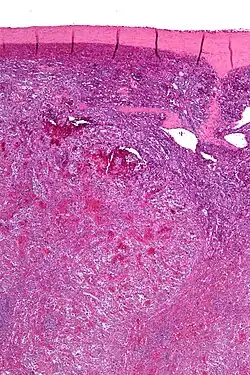

| Low magnification micrograph of a littoral cell angioma. H&E stain. | |

Littoral cell angiomas show in CT scans. They are diagnosed by pathologists by taking a sample of the tumour via Fine Needle Aspiration or Core Needle Aspiration or from a splenectomy. Histologically, they have anastoming small vascular channels and cystic spaces with papillary projections.[2]